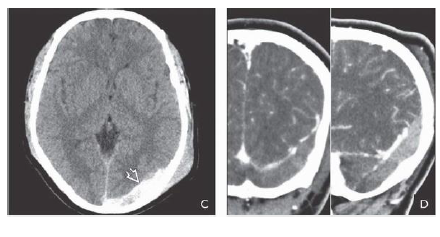

What is shon in B frontal areas 10d after the trauma?

What is shown on the 2nd box?

Repeat NECT scan 10 days later shows that the density of the EDH has decreased significantly.

Small bifrontal hypodense subdural hygromas are now seen. 2-20D. Repeat study 6 weeks after trauma

shows that the EDH has resolved. Foci of left hemisphere encephalomalacia from “contre-coup” injury

are now evident.